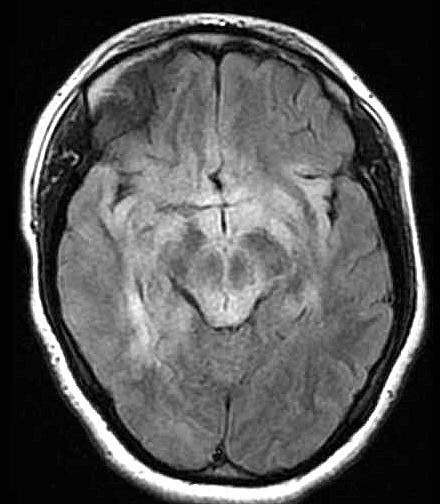

| Fem. 17a. |

| Nódulo sólido homogêneo preenchendo o III ventrículo, com limites precisos, com hipossinal em T1 e hipersinal em T2 e FLAIR, que se impregna por contraste paramagnético. Lesão menor implantada no assoalho do IV ventrículo provavelmente representa disseminação por via liquórica. |

| F. 17a. Tumor teratóide rabdóide atípico de III ventrículo. RM | HE | VIM, GFAP | HHF35, desmina, 1A4 | AE1AE3, EMA |